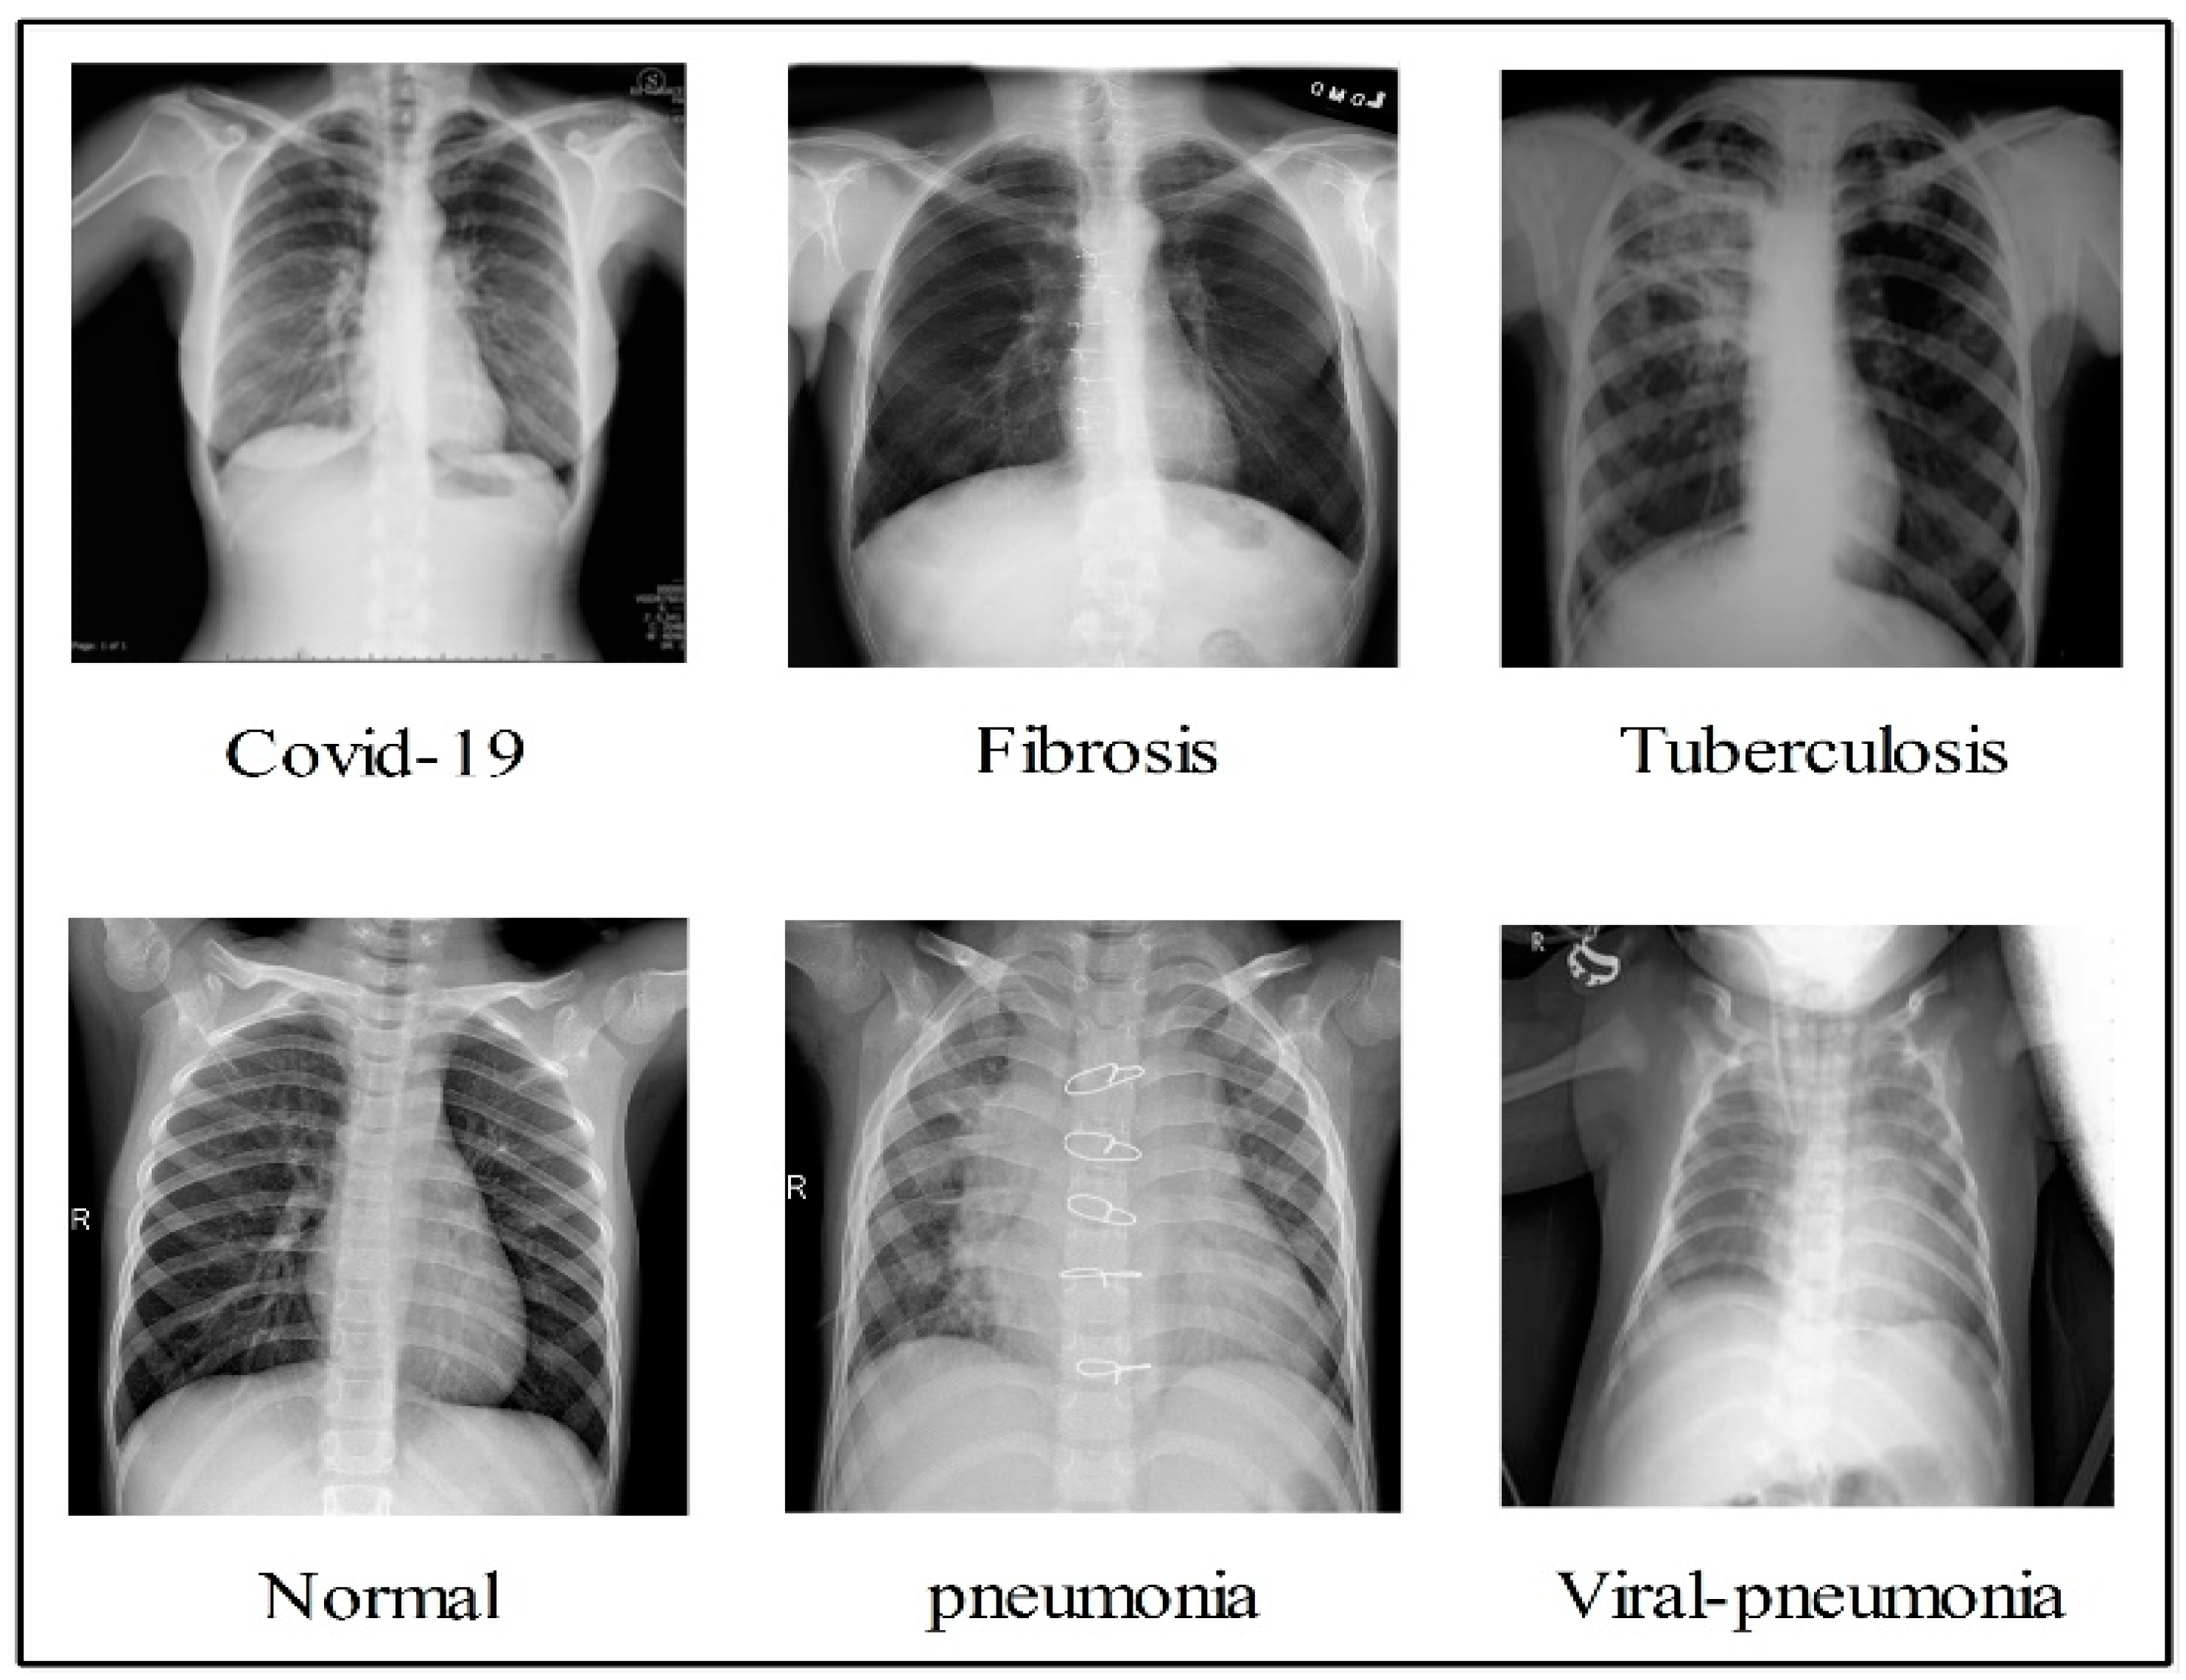

In the summary, the authors in the literature used pre-trained models with transfer learning concepts for COVID-19 classification. Few of them focused on the binary class problem, and many of them considered the multiclass problem. The deep models were trained using static hyperparameters, such as learning rate, depth section momentum, and the number of epochs. In addition, the authors selected a relatively small number of datasets for the training process. There are several challenges in effectively classifying COVID-19 using standard chest X-rays. Individuals with COVID-19 may have radiological imaging that resembles that of patients with bacterial or viral pneumonia, most notably those caused by SARS and MERS. As a result, the ability to correctly diagnose diseases by examining medical imagery has become a critical challenge. The first issue is the classification of multiple classifications, including COVID-19, viral pneumonia, lung opacity, TB, fibrosis patterns, and normal images. This is a challenge, since there are so many different types of lung diseases. These images are shown quite well in Figure 2. This figure illustrates that there is a high degree of resemblance between each image, which means that there is a chance that an incorrect classification will be made. The second challenge is the removal of redundant and useless information, which lowers the accuracy of classification, while simultaneously increasing computation time.

Figure 2.

Sample images of each class infections.